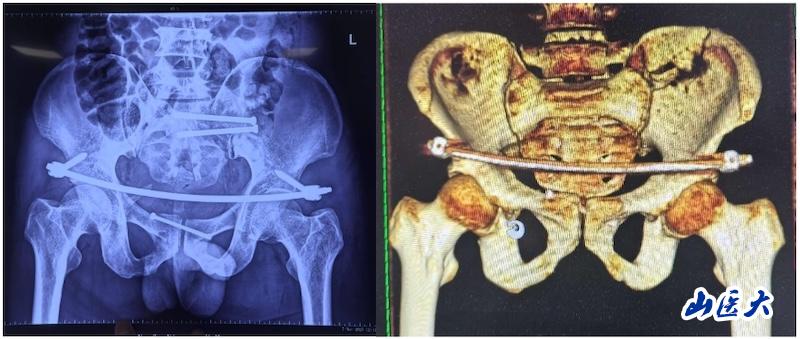

術中

據孫海鈺介紹,骨盆髖臼骨折是一種嚴重的創傷,傳統開放復位內固定術創傷大、恢復慢,而閉合復位則具有微創、出血少、恢復快等優點。隨著醫療技術的不斷進步,UCRT解鎖復位技術結合天璣機器人及O-arm術中影像系統為骨盆骨折治療提供了更加精準、微創的解決方案,該技術代表了當前骨盆骨折治療的前沿方向。

術后